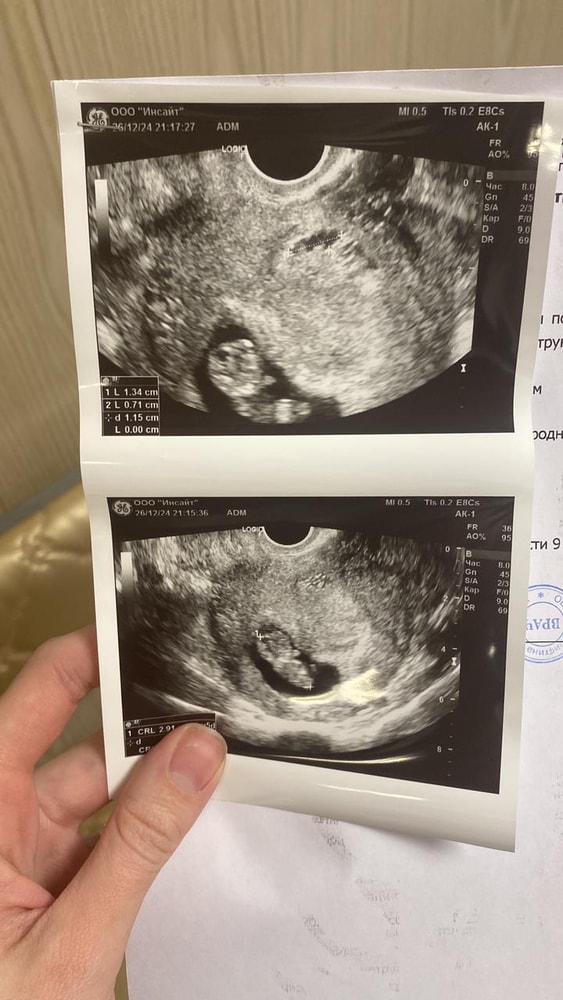

Потом одно узи, только плодное яйцо и мешочек, затем второе, и вот привет малыш🩵

Ну как обычно дальше врачи, куча анализов и ждать первый скрининг. Токсикоза не было, как такового кстати. Но не тут то было, ну не может быть все хорошо😩 Обычный день, у старшего елка в саду, сходила, пришла на работу, отработала одну клиентку, пошла в туалет и сюрприз 🤦🏻♀️ Закровило, в срочном порядке договариваюсь об узи, еду с клиенткой🙏🏻 Большое ей спасибо за это❤️Вся тряслась, сразу плохие мысли о замершей, был же опыт такой с первой самой.

И вот она красотка ГЕМАТОМА🤦🏻♀️ Все обошлось, не было госпитализации, помазало два дня и перестало.